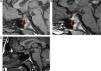

2.1) RM a los 3 meses del diagnóstico. 1A) Corte sagital sin contraste: normalización del tamaño de la adenohipófisis (flecha gruesa), persistencia de ausencia de la señal normal de la neurohipófisis y discreto engrosamiento del tallo pituitario (flecha fina). 1B) Corte sagital con contraste: realce normal de la adenohipófisis (flecha gruesa) y mayor del esperado en infundíbulo patológico (flecha fina). 2.2) RM a los 10 años. C) Corte sagital sin contraste: normalidad del tamaño de la adenohipófisis y tallo pituitario con ausencia de la señal normal de la neurohipófisis.

Niña de 9 años que consulta por poliuria y polidipsia bruscas (5-6 l/día) de 2 meses de evolución, sin pérdida de peso, alteración subjetiva del crecimiento, cefalea, alteraciones visuales, galactorrea ni otra sintomatología. Exploración física, incluido fondo de ojo, normal con talla 134cm (–0,7 DE), IMC 19,8kg/m2 (0,3 DE), estadio puberal 1 Tanner y talla diana 162,5cm (–0,2 DE). Estudio analítico: marcadores tumorales sanguíneos y anticuerpos-antihipófisis negativos; función hipofisaria con déficit de hormona antidiurética en el test de restricción hídrica, respuesta patológica de hormona crecimiento (GH) en 2 tests farmacológicos de estímulo (test de hipoglucemia insulínica y ornitina con picos de 2,6 y 2,2ng/ml, respectivamente), IGF1 233,9ng/ml (VN=117-771) e IGFBP3 1,75ng/ml (VN=1,58-3,99), sin otros déficits hormonales; líquido cefalorraquídeo con bioquímica, citología y marcadores tumorales normales. Estudio radiológico: radiografía lateral craneal y gammagrafía ósea sin alteraciones; RM con aumento del volumen adenohipofisario, engrosamiento y marcado realce del infundíbulo y ausencia de señal hiperintensa de neurohipófisis (fig. 1). Con el diagnóstico de presunción de infundíbulo-hipofisitis-linfocítica (INHL) se realizó seguimiento clínico estrecho con tratamiento específico para la diabetes insípida (DI) y controles periódicos de RM craneal para evaluar la necesidad de completar estudio con biopsia. A los 3 meses se detectó mejoría radiológica, con normalización del tamaño de la adenohipófisis, discreto engrosamiento del tallo y persistencia de ausencia de la señal normal neurohipofisaria (fig. 2.1 y 2.2). El déficit bioquímico de GH revirtió en el test de estímulo realizado a los 6 meses, siendo el crecimiento e inicio y posterior desarrollo puberal normales, con talla adulta 164cm (0 DE), menarquia a los 126/12 años y posteriores reglas regulares. La imagen patológica de hipófisis y tallo se normalizó al año de la seguimiento y 10 años después se mantiene normal, permaneciendo únicamente la ausencia de señal neurohipofisaria (fig. 2.2). Sigue precisando tratamiento con vasopresina para controlar la DI.